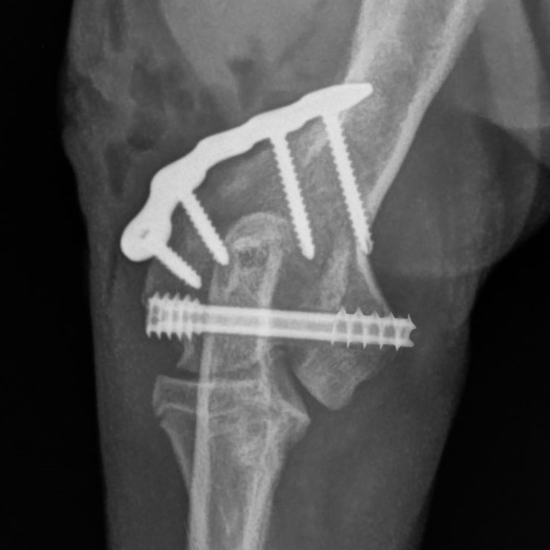

This course will explore the cannulated headless compression screw system, including its design, materials, and surgical applications. Participants will gain insights into the indications for these implants, such as elbow condylar fractures, ununited anconeal process (UAP), and hip procedures.

• Identify appropriate clinical indications for the use of headless compression screws, including elbow condylar fractures, ununited anconeal process (UAP), and hip procedures.